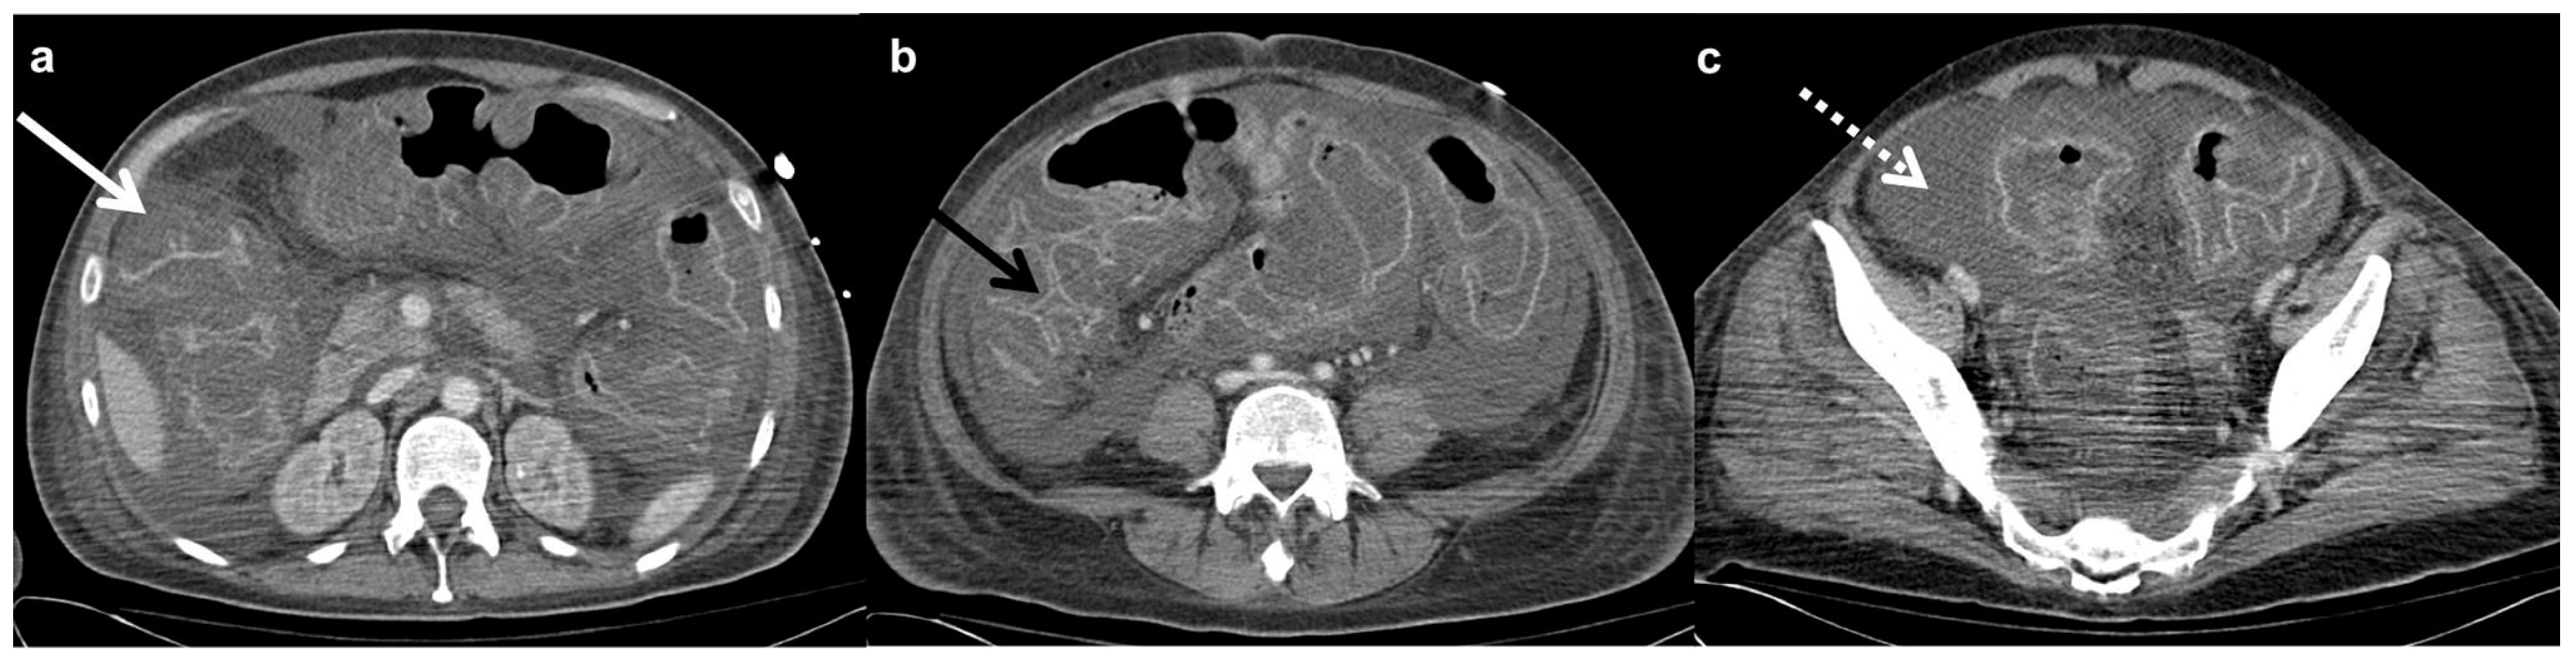

3.1.2. Computed Tomography

3.1.3. Ultrasonography